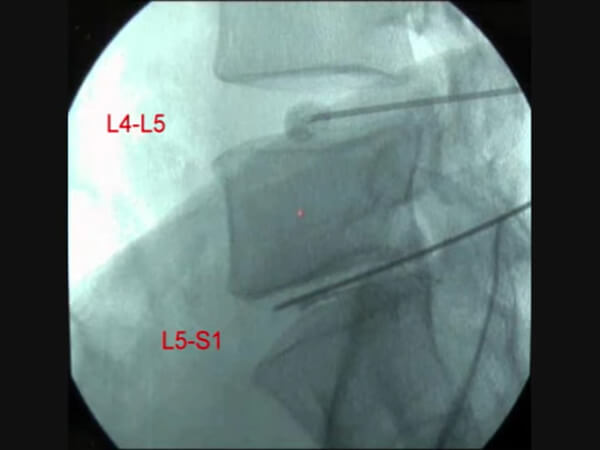

局所麻酔下で椎間板内にDiscoGel®を挿入します。

フランスでDiscoGel®を取り入れた低侵襲の腰痛治療に従事している第一人者のコールマン医師の解説動画です。動画内(1:17~)でコールマン医師は「左の患者は明らかに椎間板ヘルニアがあり、広範囲脊柱管狭窄症も合併している場合、DiscoGel®は効果がないので外科的手術が適応となります。右の患者も同様で、椎間板ヘルニアと強い不安定性(すべり症)が見られるため手術が必要であり、DiscoGel®の適応ではありません。」と述べています。